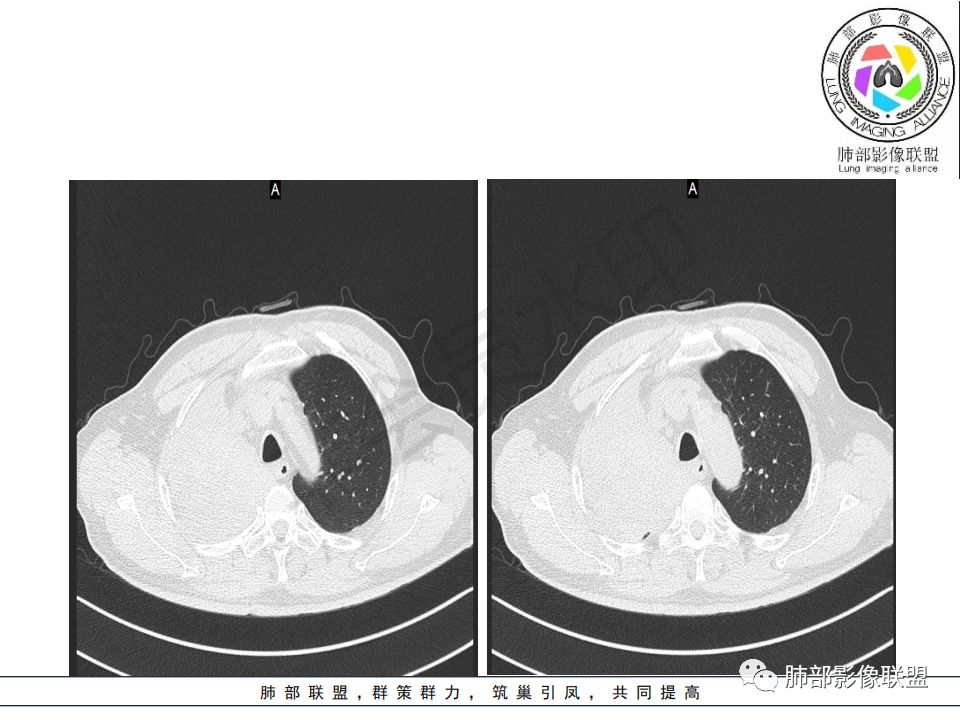

病史:男.77岁,咳嗽1月;干咳,少许白痰,无发热,2013胃癌术后,角蛋白24.65(0-3.07),SCC和proGRP不高;

影像:影像右侧大支气管阻塞,临床没有症状或很轻微,要想到胃腺癌转移;胸壁代偿好,透亮度稍低不明显,慢性过程;34.8-52.5HU,主病灶支气管前壁另有1结节,都做成增强两期了,动脉期较平扫有强化;

晨读病例:老年男性,症状轻,右侧胸廓略塌陷,右肺主支气管内外软组织影,支气管变窄截断,右肺上叶不张,其内见细砂样钙化,周围看见小结节,右肺门看见一淋巴结稍大,增强不均匀强化,胃癌病史,常规考虑:转移,或原发肺恶性鳞癌。鉴别支气管TB?

这里面是少许的泥沙样钙化吗?密度有些高

降主动脉的是噪声。病变内我总看着有小斑片的略高密度

1.右肺上叶较大块影,密度不均,轻度强化并见低密度区,所属支气管截断并腔内突入,是符合肺鳞癌的影像学特征和生物学行为的。